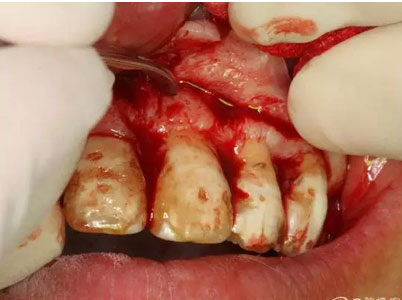

圖10.翻開粘膜瓣發(fā)現(xiàn)有唇側(cè)部分骨壁不規(guī)則缺損。

圖11.逐漸去骨薄如蟬翼的骨壁,暴露出完整的囊壁